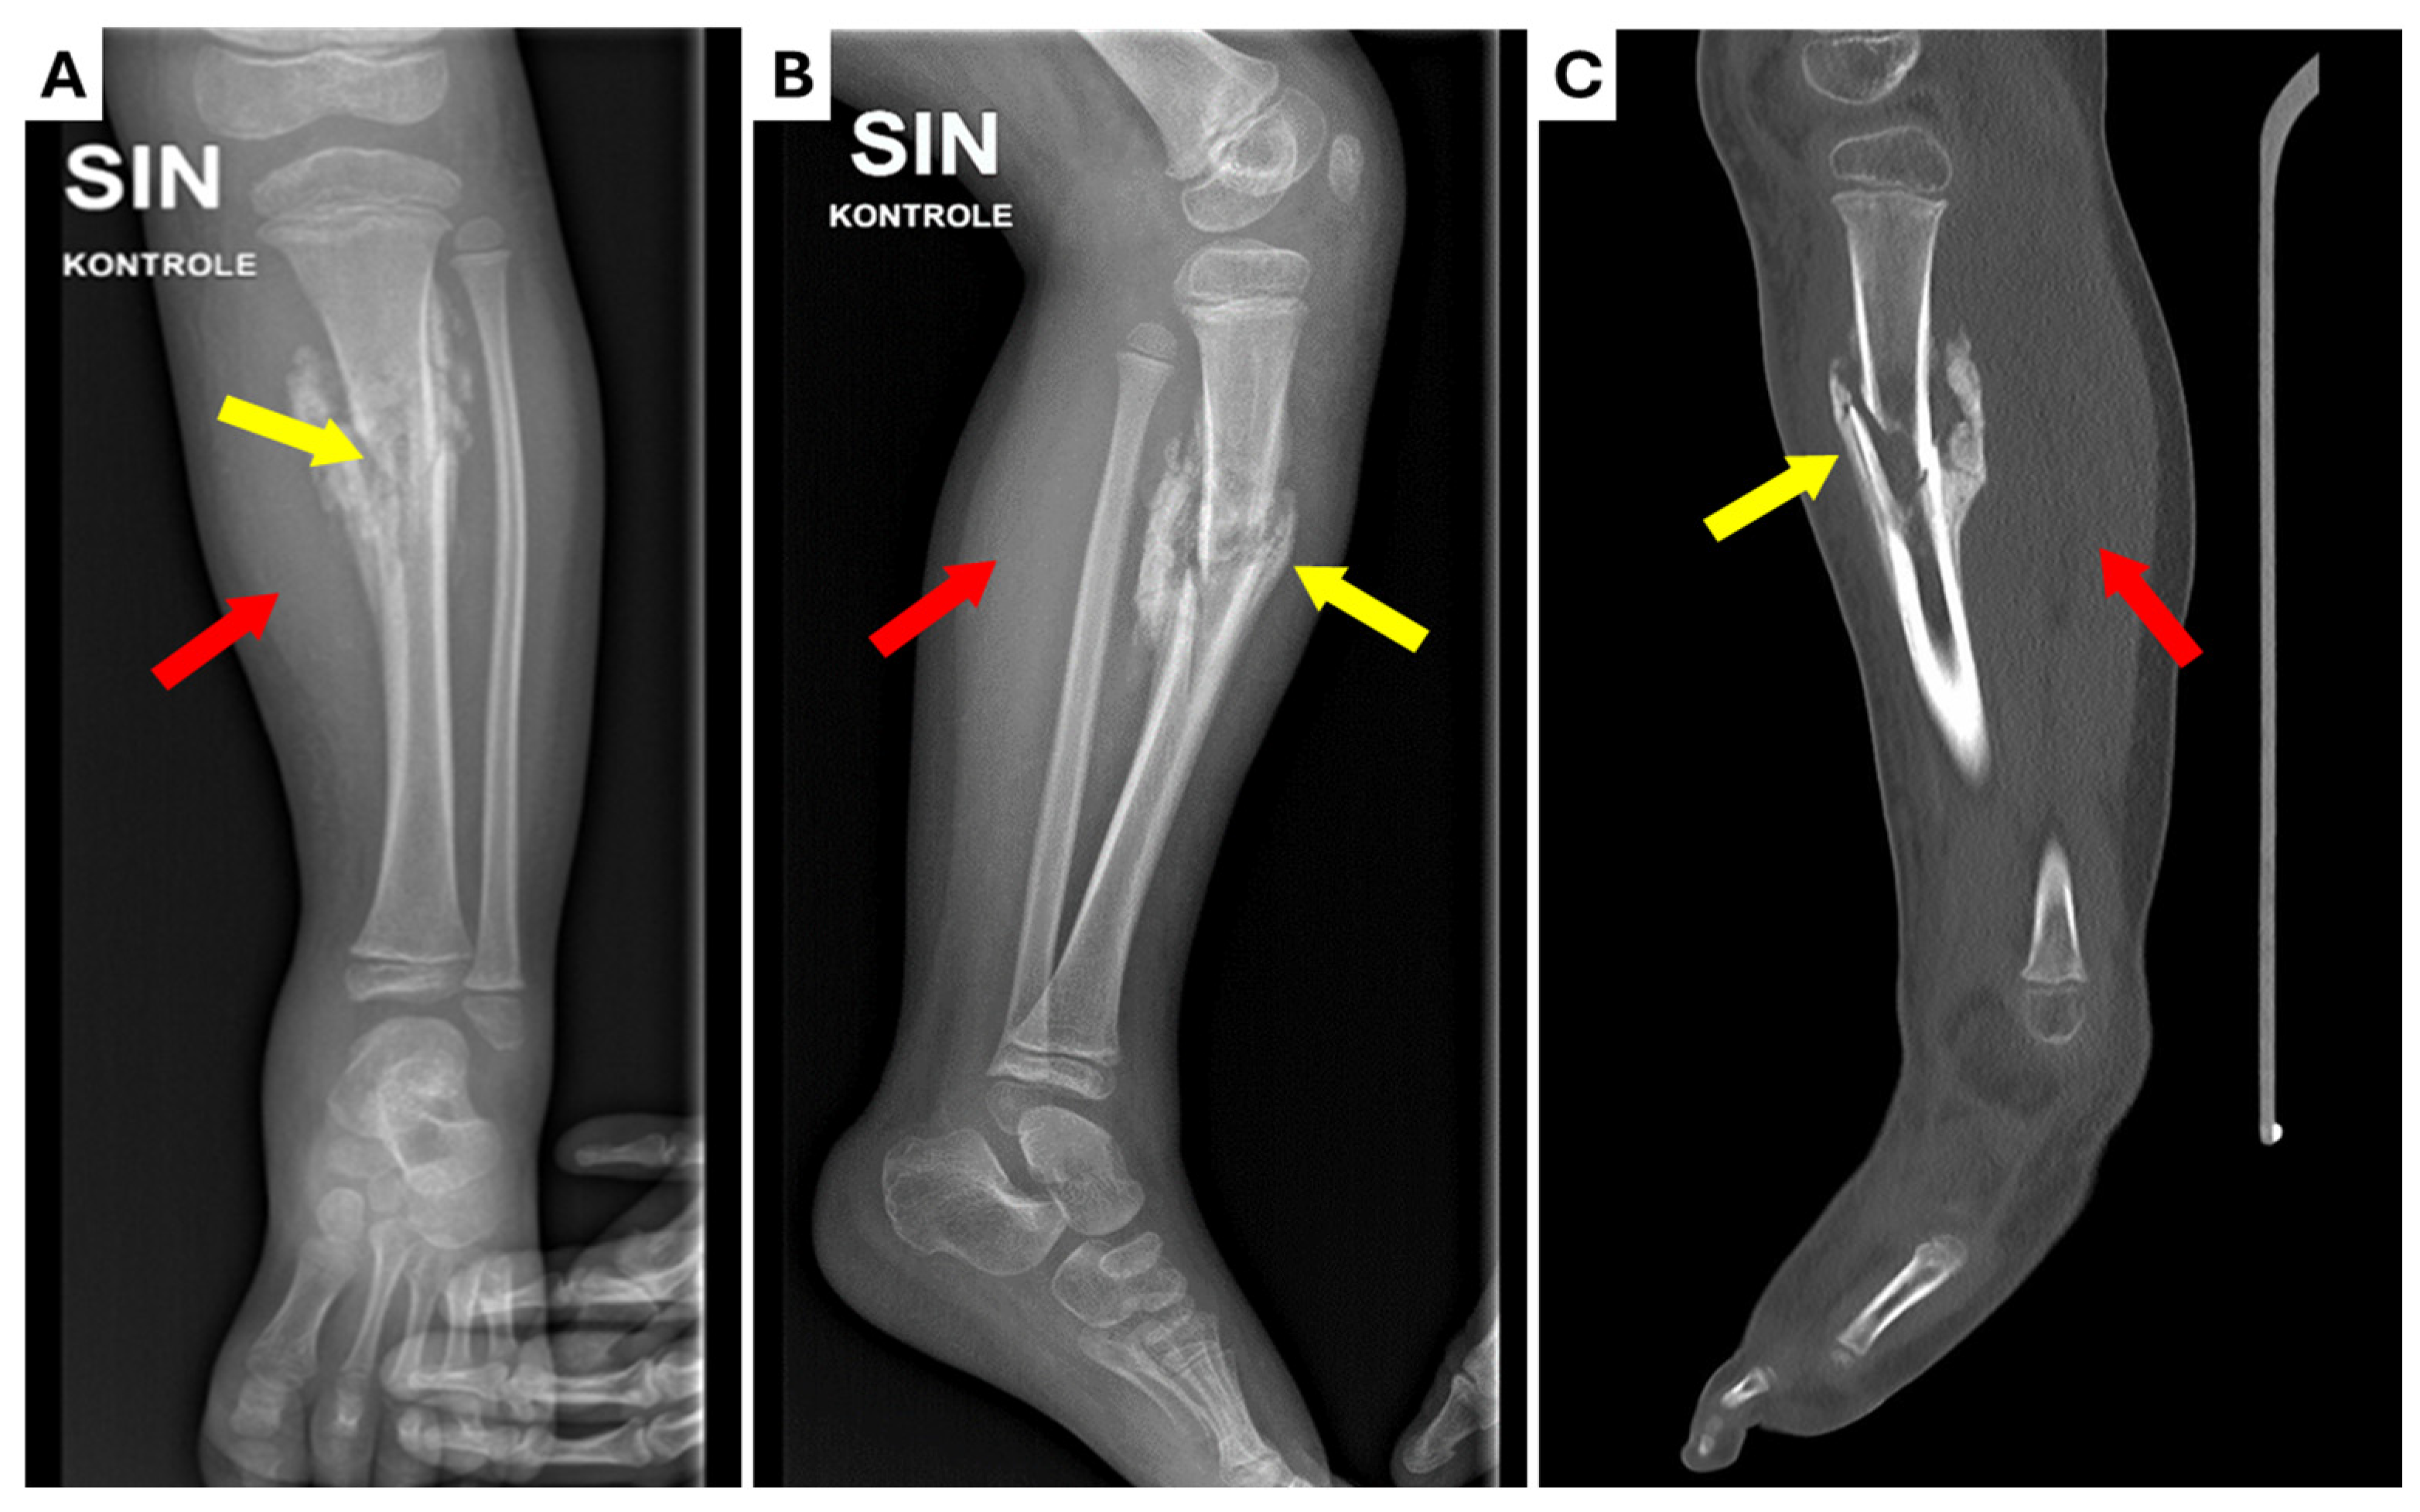

Figure 1.

Radiological examinations performed at the Regional Hospital. (A) X-ray anterior–posterior projection; (B) X-ray lateral projection; (C) computed tomography (CT) scan of the lower left leg. Marked sclerotic hyperostosis in soft tissue (red arrows) around the fracture zone and non-union of tibial mid-diaphyseal fracture (yellow arrows) with moderate angular deformation (~15o) can be seen.